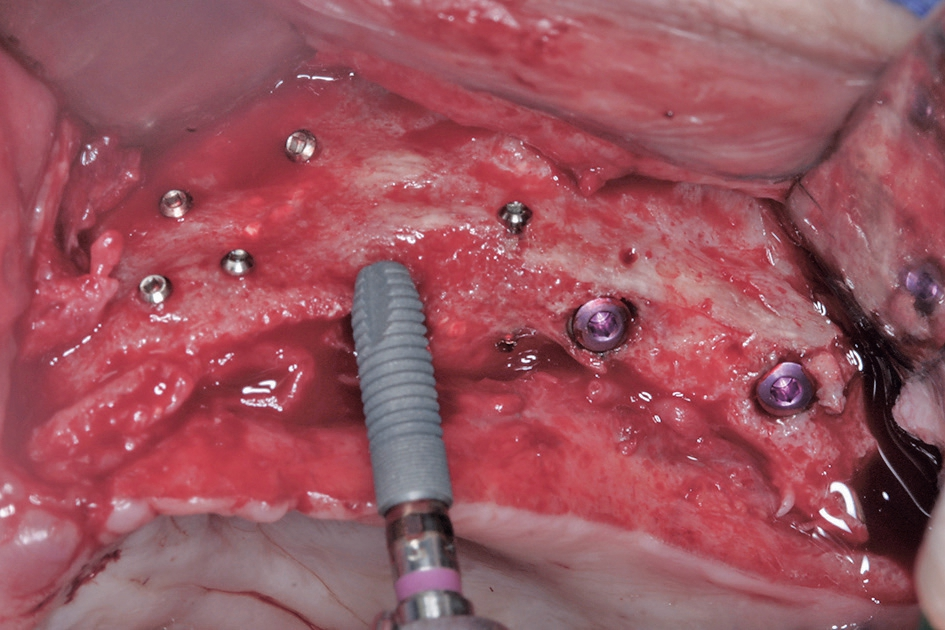

Vor dem zweiten OP-Eingriff nach 4 Monaten wurde im Labor eine Bohrschablone angefertigt. Zudem wurde ein DVT angefertigt, um im Sinne eines Backward planning die ideale Implantatposition planen zu können. Bei Eröffnung des augmentierten Kieferbereiches zeigte sich im augmentierten Bereich eine gute Regeneration und Revaskularisierung des Knochens (Abb. 14 bis 17). Sechs Implantate konnten somit in den augmentierten Bereich (Astratech EV®, DENTSPLY Sirona, Mannheim) mit ausreichender Länge und Durchmesser in Form einer gleichmäßigen Pfeilerverteilung in den Kieferknochen Inseriert werden (Abb. 18).